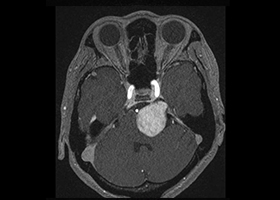

症例3)31歳男性、延髄前面巨大舌下神経鞘腫

[画像所見]

-

嚥下困難、四肢麻痺で発症しました。 -

術前 -

術後 -

術後、患者さんは元気に自宅退院されました。